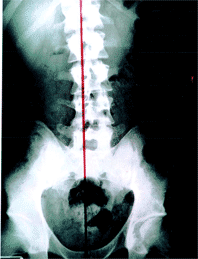

כירופרקטיקה היא שיטה יעילה ביותר לטיפול בעקמת בילדים ובמבוגרים. הטיפול הוא טבעי, יעיל ואינו כואב. באמצעות טיפול כירופרקטי והדרכה מתאימה ניתן להגיע לשיפור משמעותי בזווית העקמת. ניתן ליראות את תוצאות הטיפול המעודדות בצילומי רנטגן המתבצעים לפני תחילת הטיפולים ואחרי תקופה מדודה של טיפול כירופרקטי שגרתי. במקרים קשים במיוחד ניתן לשמר את העקמת במצבה הנוכחי, למנוע את החמרתה ואת הצורך בניתוח אורתופדי ובנוסף לטפל בפיצויים ביומכניים העלולים להיגרם כתוצאה מהעקמת בשאר חלקי והמפרקים בגוף.

ד"ר לכירופרקטיקה מאתר, מאבחן ומטפל בעקמת פונקציונלית וגם בעקמת מבנית. לאחר ביצוע צילום רנטגן של עמוד שדרה מלא במצב עמידה ובדיקה כירופרקטית, יכול הכירופרקט למדוד את זווית העקמת ולראות את מצבו הכללי של עמוד השדרה של המטופל. בכירופרקטיקה אנו מטפלים ישירות בבעיה המבנית. לאחר אבחון מדויק של העקמת וסוג העקמת נבנה תכנית המותאמת אישית למטופל. מטרת הטיפול היא לשפר את העקמת ולמנוע בעיות נוספות מלהיווצר כתוצאה מהשפעת העקמת על תפקוד עמוד השדרה והמפרקים בגוף: